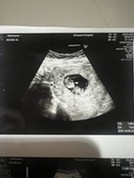

ปีก่อนเราก็แท้งคุกคามแล้วหลุดค่ะ ตอนนี้10วีคแล้ว เลือดไม่ออก คัดเต้านม อาการแพ้ท้องมาเต็ม ภาวนาให้รอบนี้ลูกเกาะแน่ๆยัน40วีคเลยค่ะ ภาพนี้ของเราซาวผ่านช่องคลอดตอน8วีค ได้ยินเสียงหัวใจด้วยค่ะ 🥰

บ้านนี้5สัปดาห์ เห็นถุงตั้งครรภ์และตัวอ่อนแล้วคะ ท้องแรกเราแท้งคุกคาม แต่พออีกเดือนก็ท้องใหม่ตอนนี้น้องได้10เดือนว่าแล้วคะ

บ้านนี้ไปครั้งแรก 5 สัปดาห์ ยังเป็นถุงอยู่ค่ะหายากมากด้วย เพราะอยู่ต่ำ หมอนัดอีกทีตอน 11 สัปดาห์ เห็นเป็นตัวเลยค่ะ 🥰

บ้านนี้ไปฝากตอน6สัปดาห์ยังไม่เจอค่ะมีเเต่ถุงตั้งครรภ์เเต่คุณหมอนัดอีกทีประมาณ8สัปดาห์ก็เจอเเล้วค่ะ